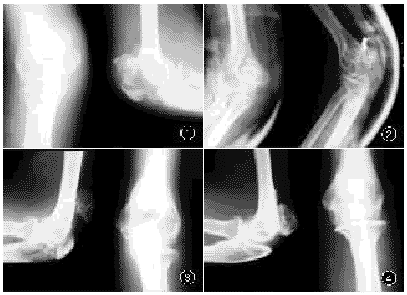

图1 左侧肘髌形成伴粉碎性骨折 图2 左侧肘髌骨折内固定术后当天摄X线片

图3 右侧肘髌形成,尺骨鹰嘴骨不连续 图4 患者女儿右肘X线片所示:肘髌形成。